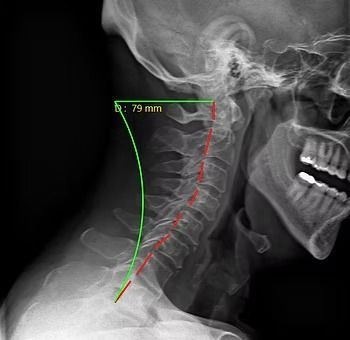

Starting off, we're going to be looking at the side of the neck. With every patient, the first thing we're looking at is the curvature. We're looking at this green curvature line and that's where we ideally want to see the bones of the spine aligned. When we're looking at the red line here next to the green one, that's actually the patient’s alignment right now. You can see that it's straightened out and we don't have as much of that natural curvature that we're looking for in the cervical spine. The second thing we analyze is the amount of space in between the bones or vertebrae. Near the top of the cervical spine, you can see how the spaces are thicker and then when you get down to the lower cervical vertebrae, they're thinner. What is happening here is the disc space is decreasing and that's important to notice because it is the first sign of degeneration in the spine.

Cervical X-Ray patient standing normally, looking straight ahead